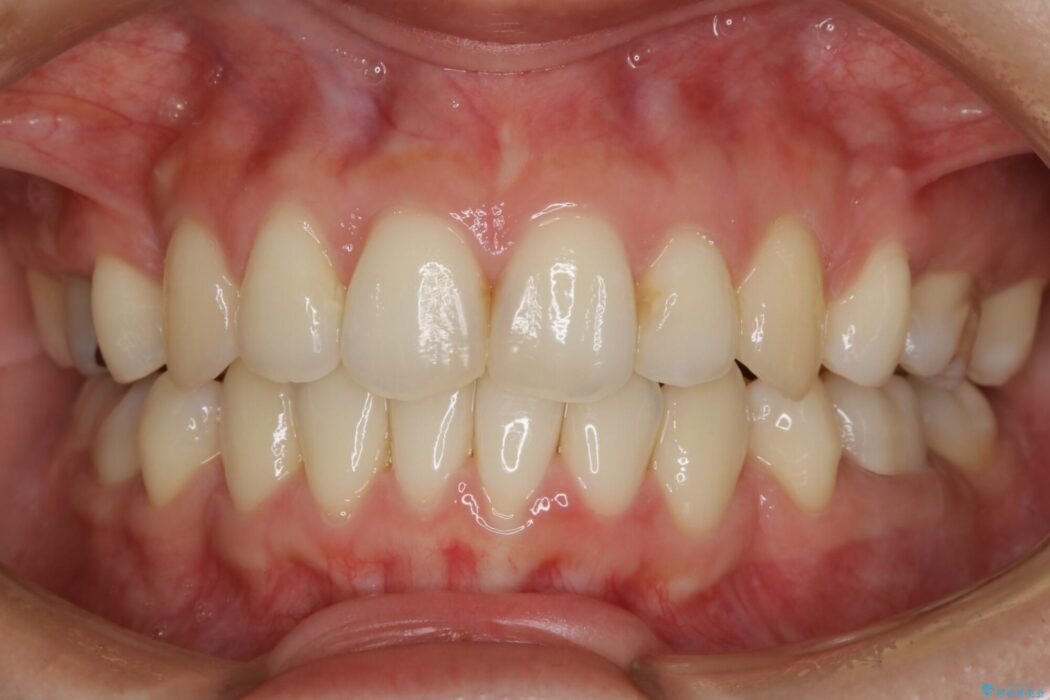

笑った時に見えるガタついていた見栄えが改善されて歯列弓もきれいな形に整い、患者様にはご満足いただけました。

従来の矯正治療では抜歯スペースなどの大きな移動のコントロールはワイヤー装置の方が適しているとされてきました。しかし、年々マウスピース装置の質が向上していることもあり、最近では抜歯した場合にマウスピース装置を使用することも増えてきました。

ですがそれを踏まえても、マウスピース装置だけできれいな歯並びへ抜歯矯正できる症例は確実に増加傾向にあると思います。